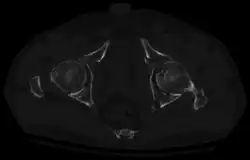

X-ray visualization is best done in Antero posterior view and Iliac and obturator oblique views. In CT scan the characteristic feature is that the fracture line runs from front to back. CT scan also helps in identifying impaction of bone pieces and if there are pieces in the joint

To understand the fracture pattern of a fractured acetabulum, it is essential to have minimum three x-ray views, though use of CT scan with 3-D reconstruction of images has made understanding of these fractures easier.

In all cases, CT scan can assist in identifying impacted bone pieces, which may be found within the joint, and MRI may be done to identify the extent of potential injury to the sciatic nerve.